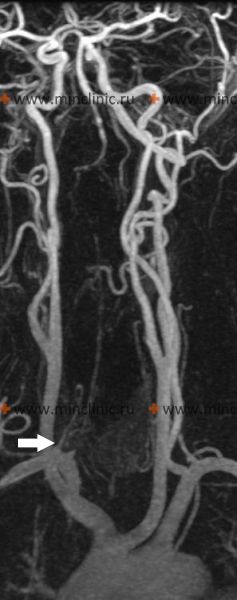

Атеротромботическое поражение вертебрально-базилярной системы и бассейна задней мозговой артерии

На границе между мостом и продолговатым мозгом две позвоночные артерии сливаются и образуют основную артерию. Основная артерия делится дальше по ходу на две задние мозговые артерии в межножковой ямке. Каждая из этих крупных задних мозговых артерий отдаёт большие длинные и короткие огибающие ветви, а также мелкие глубокие пенетрирующие ветви, снабжающие кровью мозжечок, продолговатый мозг, мост, средний мозг, гипоталамус, таламус, гиппокамп, медиальные отделы височных долей и затылочные доли головного мозга.

Существует предрасположенность определённых участков позвоночных, основной и задних мозговых артерий к атеросклеротическому поражению. Чаще всего страдают атеросклерозом начальные сегменты обеих позвоночных и проксимальная часть основной артерии. Кроме того, отмечается тенденция к образованию атеросклеротических бляшек в начальных отделах позвоночных, основной и задних мозговых артерий.